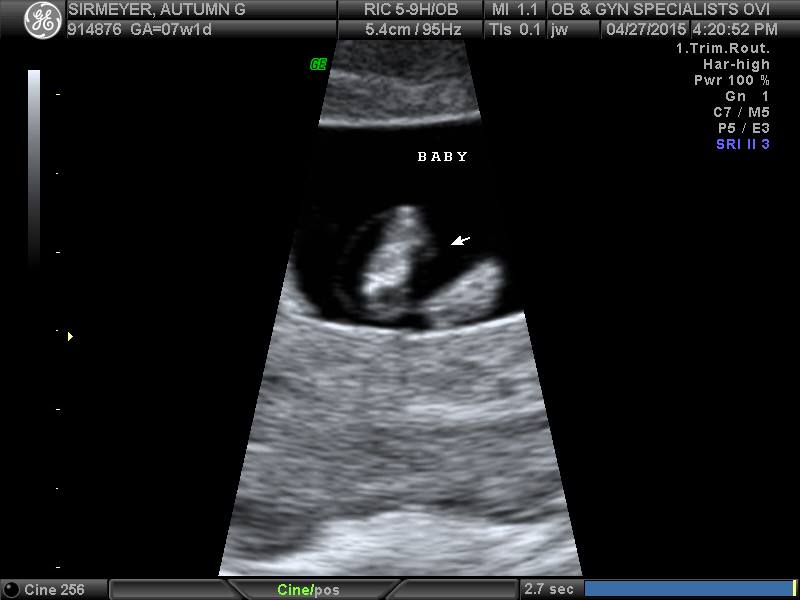

The first ultrasound of our little peanut.